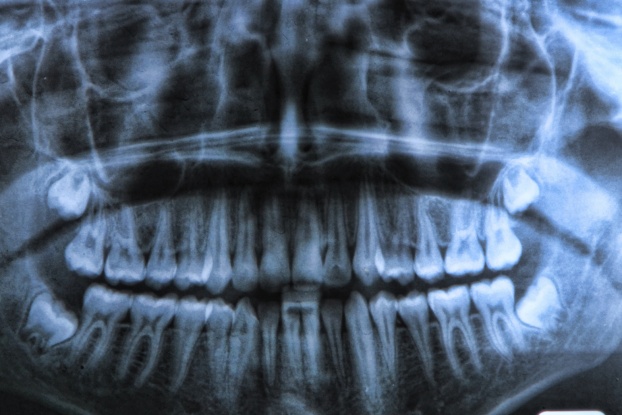

4. Răng khôn

Răng khôn được coi là một trong những bộ phận mang tính chất “di tích” – một bộ phận tàn dư còn sót lại sau một quá trình tiến hóa dài dằng dặc. Chúng đã từng được sử dụng vào một mục đích nào đó, nhưng giờ đây, chúng đơn giản chỉ là những cơ quan chưa bị quá trình tiến hóa loại bỏ. Bởi vậy, đây không hẳn là một ví dụ về sự sai lầm của tiến hóa, nói đúng hơn, chúng đã bị tiến hóa “bỏ sót”. Và sự thiếu sót này đồng nghĩa với việc rất nhiều người trong số chúng ta phải đối mặt với những ngày tháng kinh khủng khi chúng ta chẳng thể làm gì khác ngoài việc ôm mặt đau đớn và ăn cháo qua ngày.

Vấn đề nằm ở chỗ, kích thước khoang miệng của con người đã từng lớn hơn hiện tại rất nhiều. Khi xương hàm rộng hơn, chúng có thể chứa được nhiều răng hơn, và đã có lúc, chúng ta thực sự cần đến những chiếc răng khôn đó – nhai vỡ những thứ cứng rắn như xương, hạt, cũng như những miếng thịt sống và dai trước khi nấu nướng trở thành một phần trong cuộc sống.

Nhưng khi con người ngày càng tiến hóa về mặt trí tuệ, nhu cầu ăn uống của chúng ta cũng đã thay đổi rất nhiều. Thêm vào đó, sự thay đổi cấu trúc và kích thước hộp sọ, đặc biệt là kích thước xương hàm đã khiến răng khôn trở nên không còn chỗ đứng như trước. Việc mọc lên rất muộn (vào khoảng những năm đầu của tuổi 20, đây cũng là lý do tại sao chúng được gọi là răng khôn) gây ra quá nhiều rắc rối – đau đớn và tệ hơn là các nhiễm trùng tại chỗ đã khiến răng khôn được xếp vào danh sách này.